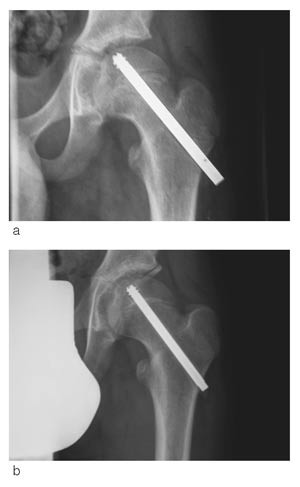

Vi fikk i 1992 spesialkonstruert en skrue som en modifisert Olmed-skrue (De Puy) og har siden da brukt denne rutinemessig ved epiphysiolysis capitis femoris. Målet var at skruen skulle kunne tillate fortsatt vekst i collum. Skruen har kortere gjengesegment enn vanlig Olmed-skrue som brukes til fractura colli femoris, for at hele gjengesegmentet kun skal stå i epifysen. Skruen er derfor glatt over vekstskiven, slik at den kan tillate fortsatt vekst i collum.

Det har tidligere vært til dels store problemer med å fjerne skruen (13, 14). For å redusere problemer med fjerning, er gjengene skjærende begge veier (fig 1, fig 2). Vi har med denne studien ønsket å kartlegge eventuelle problemer i tilknytning til operasjonsmetode både ved innsetting og ved fjerning av skruen, hvorvidt en skrue er tilstrekkelig i forhold til ev. ytterligere glidning og om det fortsatt skjer vekst i fysen. Videre har vi undersøkt forekomst av caputnekrose og kondrolyse og klinisk resultat ved oppfølging.

For å se på hvorvidt det skjer en fortsatt lengdevekst i collum med denne fiksasjonen, har vi målt endring i distale skrueendes protrusjon ved laterale cortex, artikulotrokantær avstand samt collumlengde ved operasjon og ved oppfølging.

Vi har målt distale skrueendes protrusjon ved laterale cortex i ti hofter. Gjennomsnittlig er den redusert med 0,53 cm per år (fig 3). Dette kan kun delvis forklares med økt bredde av femur ved økt vekst. Femurs bredde ved skruens distale ende har vi målt i seks hofter og gjennomsnittlig har femurs bredde ved laterale cortex økt med 0,17 cm per år.